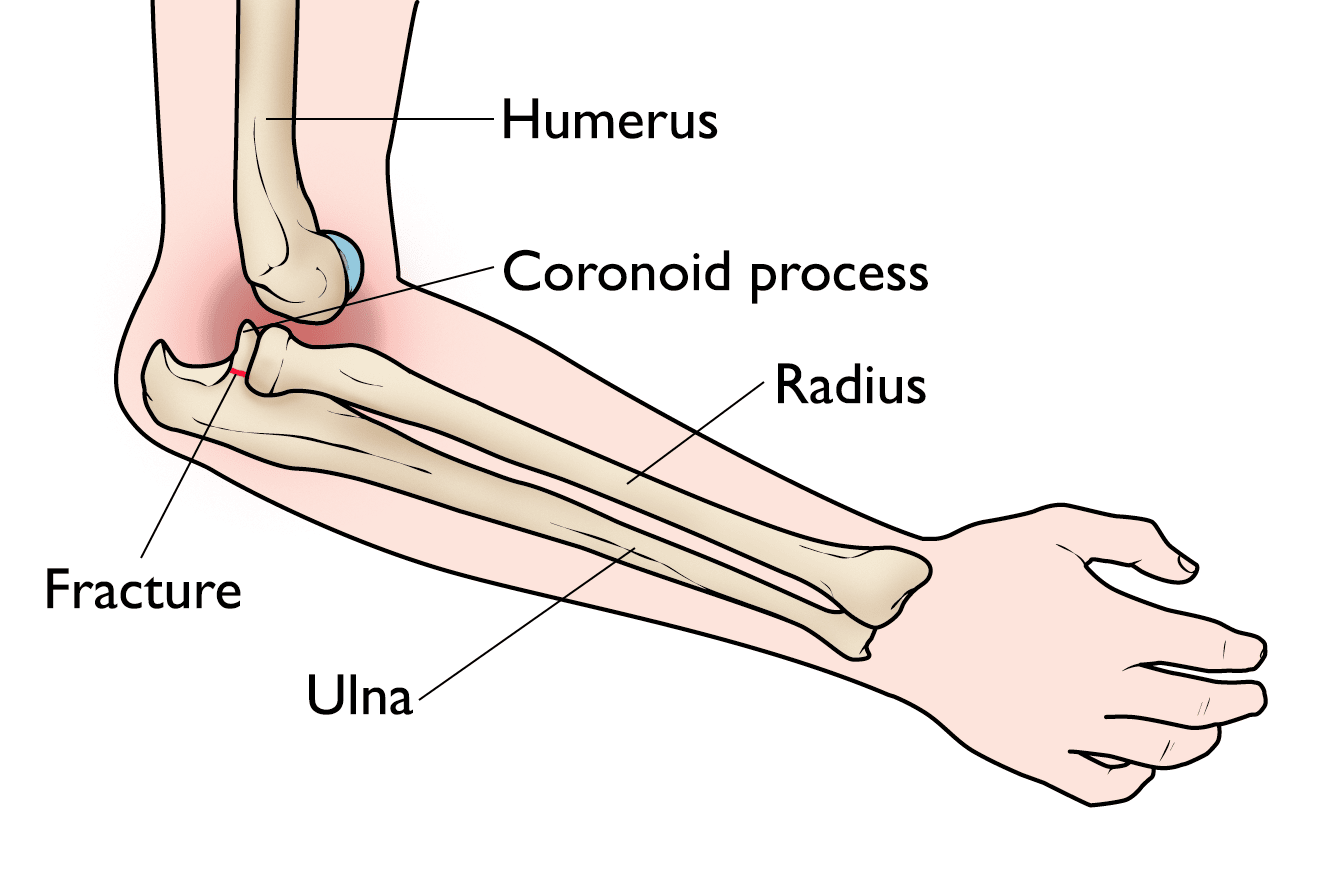

• Fracture fixation. Patients with unstable elbows with significant associated fractures require treatment to repair both the broken coronoid bone and the torn ligament. During the operation, the broken bone fragments are repositioned into normal alignment, then held together with special screws and, sometimes, a metal plate. If there are fractures of the radial head, those can be treated with similar fixation techniques, or the broken pieces can be replaced.

elbow fracture plate-and-screw fixation

This X-ray, taken from the front of a straightened elbow, shows a coronoid fracture fixed with a metal plate and screws.

Reproduced with permission from Steinmann SP: Coronoid process fracture. J Am Acad Orthop Surg 2008; 16: 519-529.